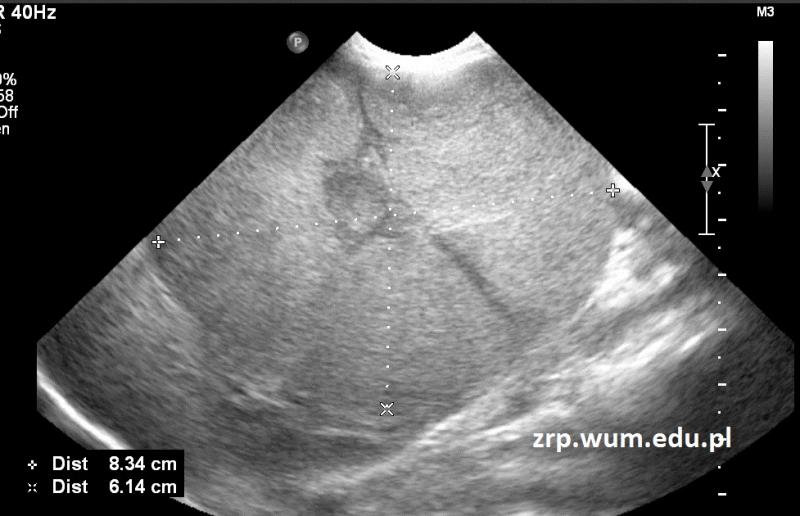

Przypadek 36: 7-miesięczna dziewczynka skierowana do IP z powodu podejrzenia guza jamy brzusznej, stwierdzonego podczas rutynowego badania przedmiotowego w trakcie wizyty kontrolnej przed szczepieniem.

Rozpoznanie: W badaniu USG uwidoczniono kulistego kształtu, dobrze odgraniczoną od otoczenia litą zmianę guzowatą, wyrastającą z dolnej części nerki prawej.

Pytanie: Jakie nowotwory należy rozważyć w diagnostyce różnicowej guza okolicy nerki u dziecka?